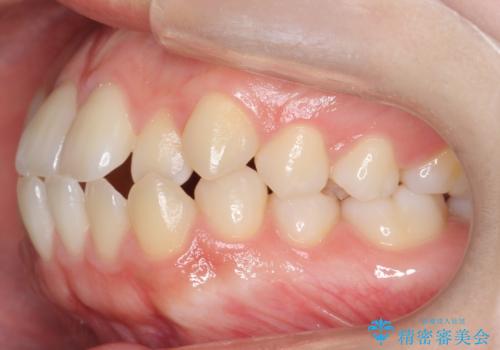

前歯、奥歯ともに反対咬合になっており、また上顎の前歯が少し突出気味でした。

時間はかかりましたがしっかりかみ合わせから治すことができました。

口元の突出も改善しており理想的な横顔になりました。